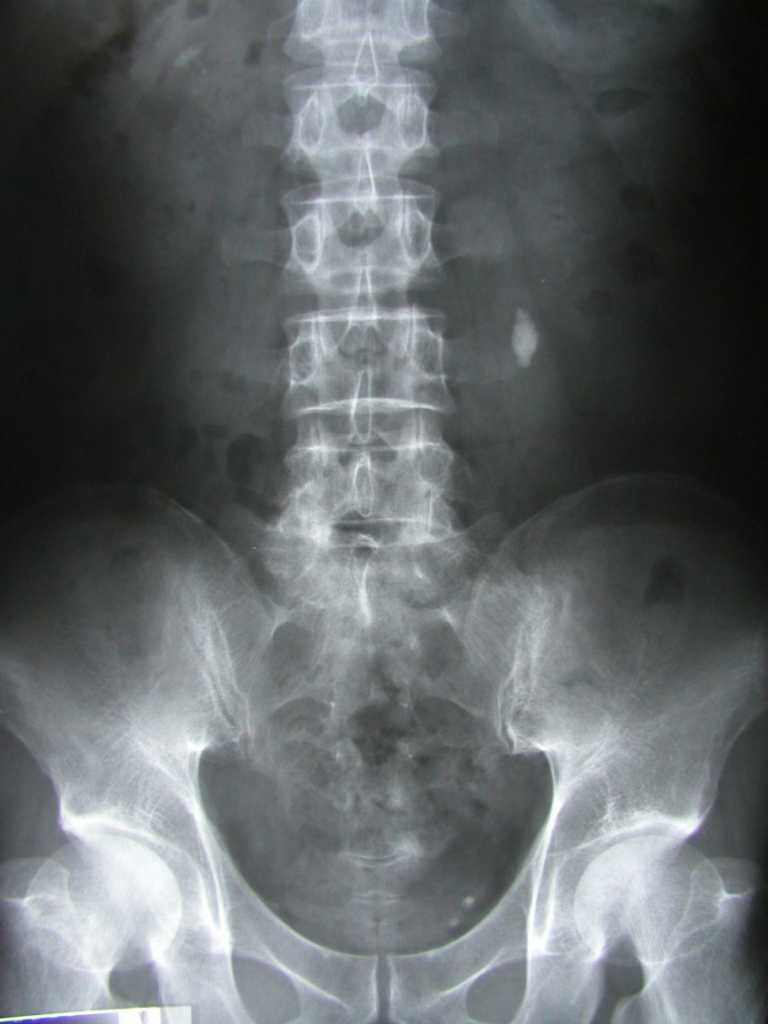

KUB 검사에서 보이는 결석 (출처 : 위키 미디어)

영상검사는 요로결석 진단에서 가장 중요하고 요로결석을 실제로 확인할 수 있는 검사입니다.

(1) 콩팥요관방광 단순촬영술(KUB) : 기본적으로 시행하는 X-ray 검사입니다. 결석의 위치, 모양, 크기를 파악하는데 도움이 될 수도 있습니다.